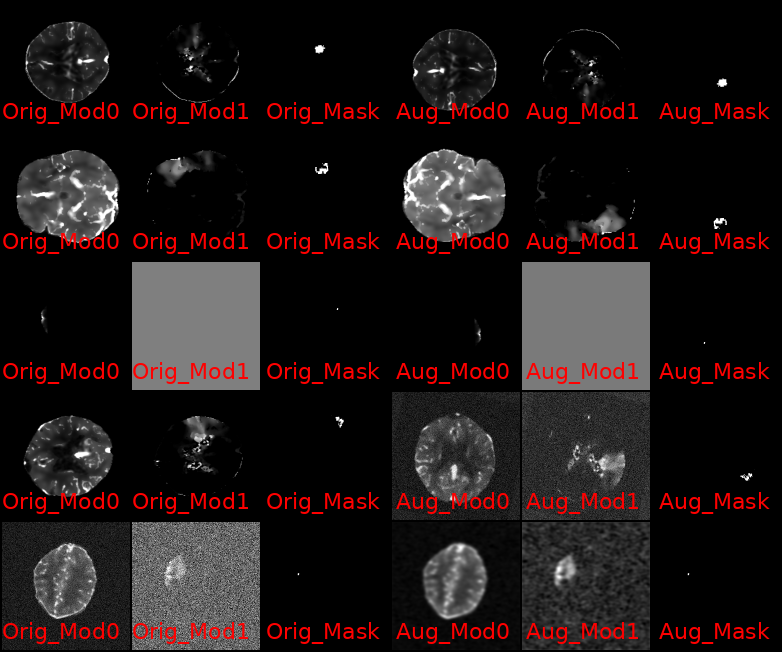

This was an juypter notebook that I broke down into components classes and files, and started adding experimental structures that would allow me to conduct configurable, extensible research into using this model for the ISLES24 Dataset as well as ported over my ISLES24 manipulation code from my existing SwinUNetR experiments.

Among the advancements that I've added to the codebase since, are the following few that I want to highlight: